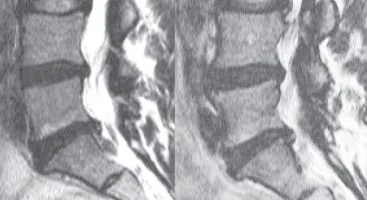

Severe Neck Degeneration & Misalignment

Ella had severe neck pain and stiffness. When the pain started traveling down her right arm, causing weakness in her hand, she became unable to work or be physically active. She had been taking pain medication for years, but the weakness...